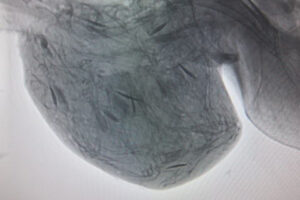

中身は何?

そのうの内部がよく見えるように、レントゲン写真の色を反転してみると、長い三日月型をした小さな粒がたくさん入っているのが解ります。実はこれ、魚の「耳石」。耳石は平衡感覚を調整する機能を持ち、頭骨の中に一対ずつ存在する炭酸カルシウムの結晶です。